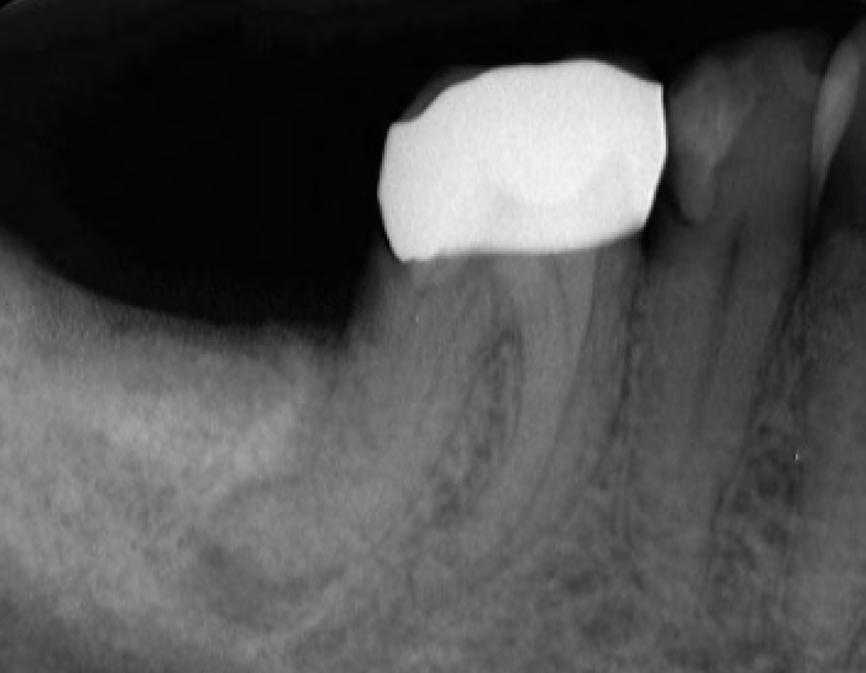

Clinical Case 3 The patient was referred to our endodontic practice for evaluation and treatment of tooth 46. Clinically #46 had an all-ceramic crown, a negative response to cold, and tenderness to percussion. Pre-op x-ray revealed #46 had a periapical radiolucency associated with the Distal root and severe D root curvature in the apical third. Pulpal Necrosis with Symptomatic Apical Periodontitis. Tooth #47 accessed, located MB, ML, and DB and DL canals. Canals instrumented with EdgeFile X7 rotary files using a crown down technique Endodontic diagnosis: Pre-Op – James A. Wealleans, D.M.D, American Board Certified Endodontist, Adj Professor, Clinician Sydney, Australia

EdgeFile X7 25.06 to resistance, then 20.06 to resistance, then 25.06 to resistance. Working length hand file to 15, 17.04 if necessary, 30.04, 35.04, 40.04. For this case, I vigorously used hand files above my typical sequence to a #35K and finished with an X7 35.04 at 500 RPM 2.6 N/cm torque. Sequence of files for ‘crowndown’ (with MAF sizes) Working lengths were determined via apex locator followed by radiographic confirmation. The canal system was obturated with bioceramic sealer (BUSA, BC Sealer). The access was immediately re- stored with a fiber reinforced dual cure core material. Cone-Fit EdgeEndo are hands down the best rotary instruments on the market! The flexibility and durability are unmatched! It was a seamless transition to switch and file separation became a thing of the past! – James A. Wealleans, D.M.D., American Board Certified Endodontist, Adj Professor, Clinician Sydney, Australia